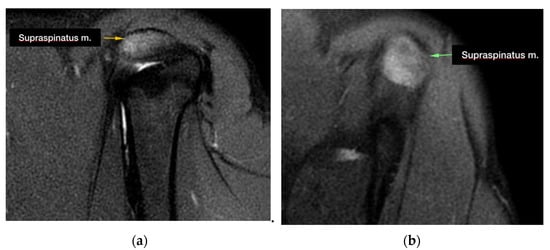

During the MRI evaluation, a marked hyperintense signal localized to the insertion of the supraspinatus muscle was found in all of the examined shoulders in the STIR images (Figure 1).

The tendon of the supraspinatus muscle was severely enlarged in 3 out of 27 of the cases. Five MRI images revealed compression of the biceps brachii tendon sheaths, while 10 out of 27 of the biceps brachii tendon sheaths were distended. Moreover, an effusion was present in the sheath of the tendon of the infraspinatus muscle in 1 one out of 27 of the cases and in the sheath of the biceps brachii muscle in 1 out of 27 of the cases.

The common alteration revealed by MRI in patients affected by nonmineralized tendinopathy is an enlargement and a marked increase in the signal in the insertion area of the supraspinatus tendon above the greater tubercle of the humerus in the STIR sequences. In a recent study, it was noticed that pathologic tendons, in addition to an alteration in the signal, also present an increase in volume [22]. In our population, only 3 cases out of 27 had an increase in the volume in addition to an alteration in the signal.

Figure 1. Supraspinatus tendon appearance during MRI imaging acquisition: (a) hyperintense signal at the level of the insertion of the supraspinatus tendon in the STIR images (sagittal plane); (b) hyperintense signal at the level of the insertion of the supraspinatus tendon in the STIR images (transverse plane).